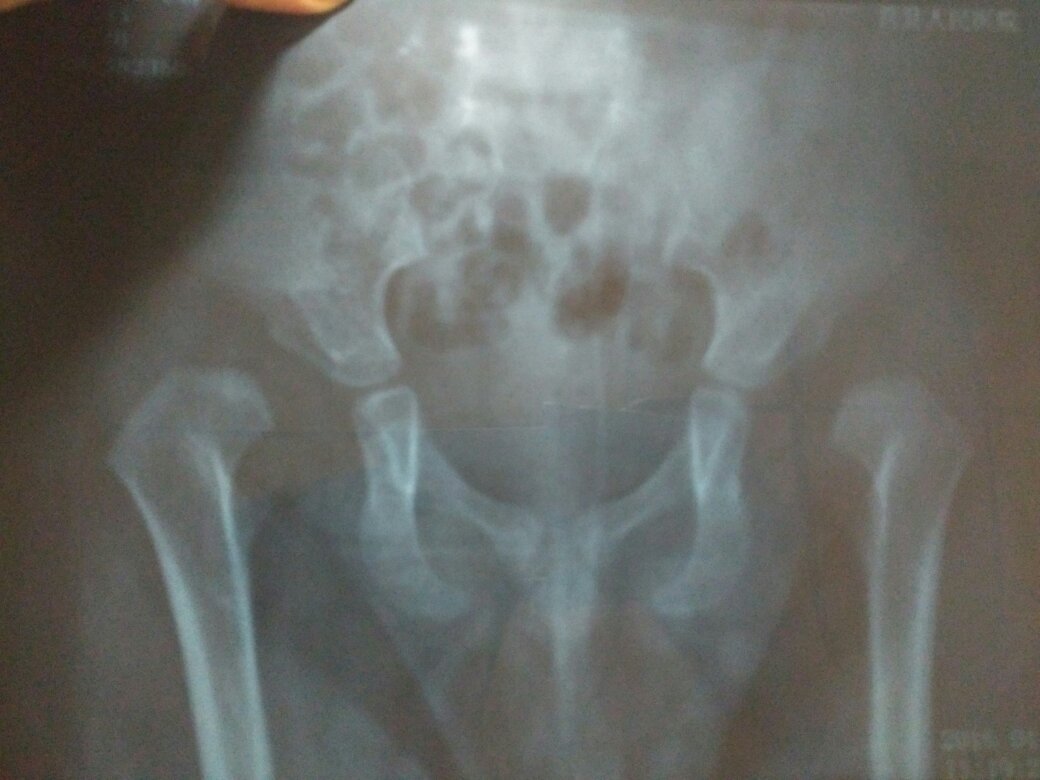

双侧先天性髋关节脱位,孩子一岁8个月了,走路跛行,怎么治疗,治疗后可像正常人一样行走吗,有没有后遗

双侧先天性髋关节脱位,孩子一岁8个月了,走路跛行,怎么治疗,治疗后可像正常人一样行走吗,有没有后遗症。很着急,在线等,请帮帮我!!